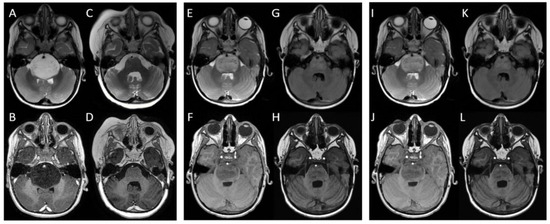

| Child n. 1 | 9 months | 6 months | 24 months |

| Child n. 2 | 6 months | 4 months | 18 months |

| Child n. 3 | 6 months | 3 months | 17 months |

| Median value ± standard deviation | 7 ± 1.7 months | 4.3 ± 1.5 months | 19.6 ± 3.7 months |